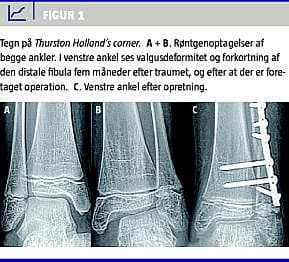

En tiårig pige kom til skade på en skiferie. Hun blev undersøgt lokalt, hvor man fandt, at hun havde smerter i og hævelse af den laterale del af venstre ankel. Hun var ikke i stand til at støtte på den venstre fod. Et røntgenbillede viste intet abnormt. På mistanke om en epifyseskiveskade af den distale fibula anlagde man en bagvedliggende skinne. Patienten blev efter få dage set på hjemstedssygehuset, hvor man havde mistanke om en epifyseskade af den distale fibula. På baggrund af dette blev patienten udstyret med en crusgips i fem uger. Efter afbandagering havde hun fortsat smerter i anklen. Klinisk var der hævelse og palpationsømhed. Patienten blev fulgt op klinisk, og på grund af manglende bedring blev der efter tre måneder foretaget en magnetisk resonans-skanning. Denne gav ikke nogen forklaring på symptomerne, men man kunne se, at der var dannet en bro i epifyseskiven. Et nyt røntgenbillede af begge ankler, der blev taget efter fire måneder, viste breddeøget afstand i det mediale ledkammer i den skadede side (Figur 1 A + B). Ved yderligere gennemgang af patientens røntgenbillede fandt man en SH type II i den distale fibula, som var helet med sammenvoksning i epifyseskiven i den distale fibula. Dette medførte forkortning af fibula i forhold til tibia og bevirkede udvikling af valgusdeformitet i anklen. Patienten blev opereret seks måneder efter skadetidspunktet. Der blev foretaget osteotomi af den distale fibula og akut forlængelse og resektion af sammenvoksningen af epifyseskiven i den distale fibula. Patienten blev fulgt i ti måneder, hvor man fandt normal akse og bevægelse i anklen, og hun var derefter symptomfri (Figur 1 C).